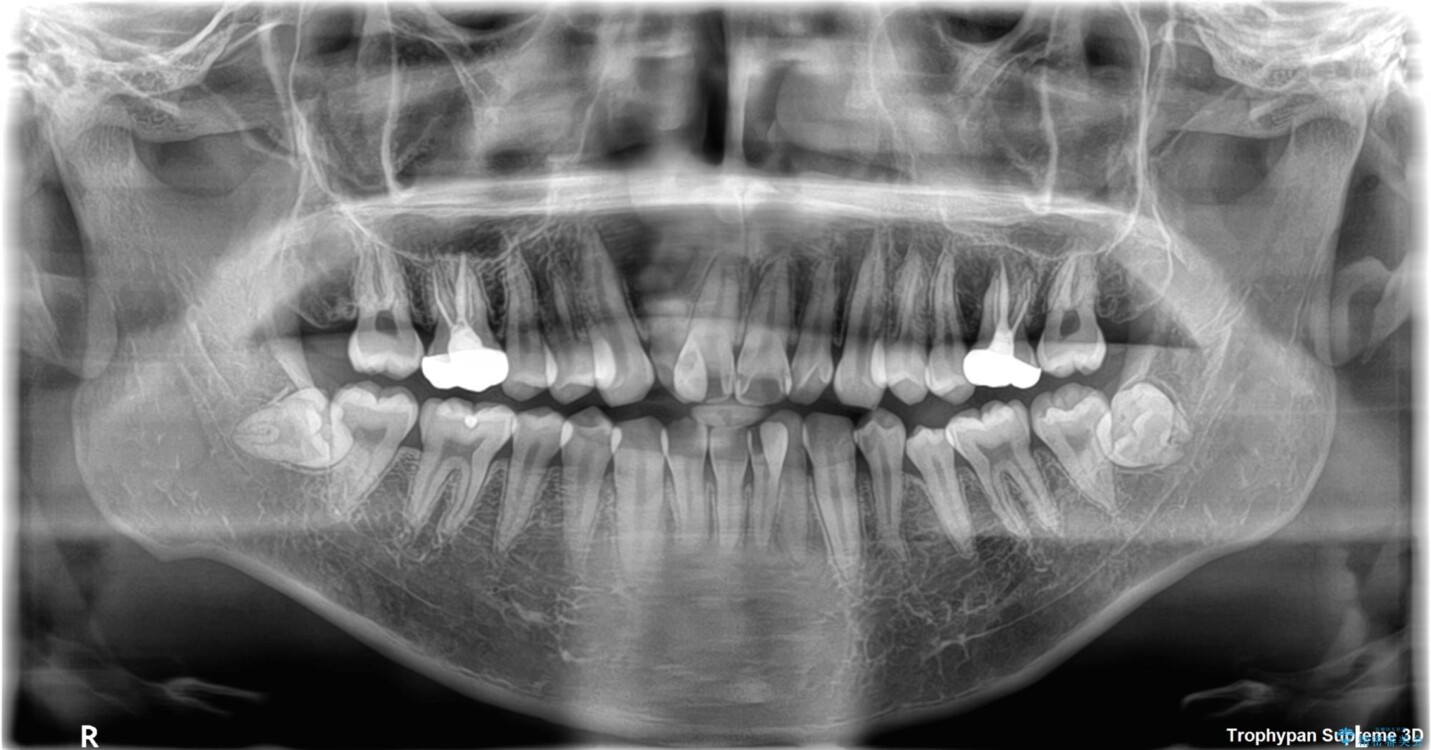

初診時の状態

・上下ともに歯がきれいに並びきらず、がたつきが見られました。

・上下の前歯の中心(正中)がずれています。

・特に上顎の幅が狭いため、下顎の歯列も内側に入り込み、歯が並ぶスペースが不足していました。

• 1年でここまで変わる!歯列のがたつきと正中のズレを改善した矯正治療(メタルブラケット×MARPE) 治療前画像